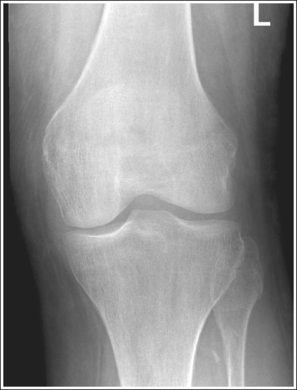

• Analysis of joint space narrowing. On an AP knee projection with adequate positioning, joint space narrowing is evaluated by measuring the medial and lateral aspects of the knee joint, which are also referred to as compartments. The measurement of each of these compartments is obtained by determining the distance between the most distal femoral condylar surface and the posterior condylar margin of the tibia on each side. Comparison of these measurements with each other, with measurements from previous images, or with measurements of the other knee determines joint space narrowing or a valgus or varus deformity. In a valgus deformity the lateral compartment is narrower than the medial compartment; in a varus deformity the medial compartment is narrower (see Images 56 and 57). Precise measurements of the compartments are necessary to ensure early detection of joint space narrowing and are best obtained when the knee joint space is completely open. If an inaccurate central ray angulation was used for an AP knee projection, the knee joint is narrowed or obscured, the intercondylar eminence and tubercles are foreshortened, and the tibial plateau is demonstrated.

The lateral knee compartment is narrower than the medial knee compartment. The patient's knee demonstrates a valgus deformity.

The medial knee compartment is narrower than the lateral knee compartment. The patient's knee demonstrates a varus deformity.